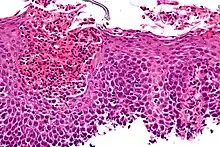

Eosinophilic esophagitis

Eosinophilic esophagitis is caused by a high concentration of eosinophils in the esophagus. The presence of eosinophils in the esophagus may be due to an allergen and is often correlated with GERD. The direction of cause and effect between inflammation and acid reflux is poorly established, with recent studies (in 2016) hinting that reflux does not cause inflammation.[6] This esophagitis can be triggered by allergies to food or to inhaled allergens. This type is still poorly understood.